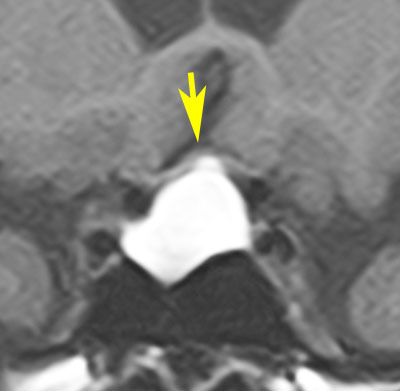

MRI画像(T1高信号のもの)

ラトケのう胞はT1強調画像で白く(左:高信号)にみえて,T2強調画像で黒く(右:低信号)にみえることもあります。前の例とはかなり違った印象です。中身は乳白色のドロドロの液体です。矢印のところは視神経交叉(左右の視神経がつながるところ)で,ラトケのう胞に圧迫されて弓形に変形しています。このくらいの視交差の変形では視野障害は出ませんし視力も低下しません。ですから,手術も何もしないで経過観察のみをします。多くの場合は,何も治療しなくて良いものです。この患者さんは無治療で経過を見ました。